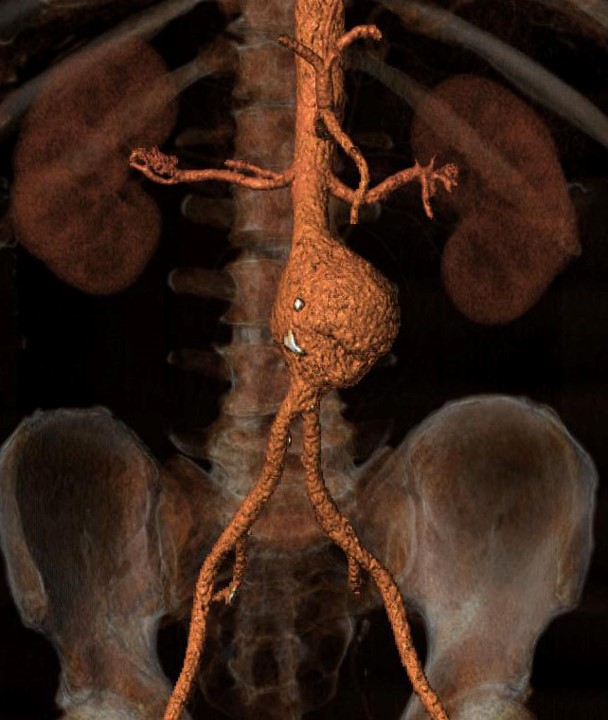

Ανεύρυσμα κοιλιακής αορτής

Ένα αορτικό ανεύρυσμα εντοπίζεται συχνά στην κοιλιακή χώρα, το λεγόμενο ανεύρυσμα κοιλιακής αορτής, και συνήθως θεωρείται ότι υπάρχει όταν υπερβαίνει τα 30 χιλιοστά. Οι αορτές με μέγεθος 25-29 χιλιοστά πρέπει να θεωρούνται εκκολαπτόμενα ανευρύσματα

Διάγνωση και παρακολούθηση με υπέρηχο

Το μέγεθος της αορτής απεικονίζεται με τη βοήθεια υπερήχου.

Ανάλογα με το μέγεθος προτείνεται αρχικά παρακολούθηση και επανέλεγχος με υπέρηχο σε τακτικά χρονικά διαστήματα ή αν το μέγεθος πλησιάσει το ανώτατο όριο τότε το επόμενο βήμα είναι η αξονική τομογραφία και ενδεχομένως το χειρουργείο